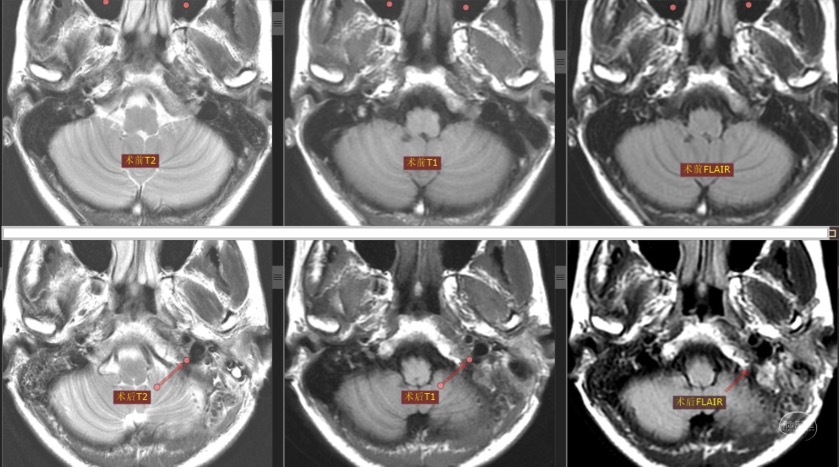

根据患者症状和体征,排除肺部病变,考虑病变定位于左侧颈静脉孔区导致左侧第Ⅹ和第Ⅺ颅神经同时受累。尽管磁共振报告“阴性”,但我们从术前CT和磁共振影像上仔细观察,还是能发现一些蛛丝马迹:CT显示左侧颈静脉孔较对侧略扩大,磁共振增强扫描显示左侧岩下窦汇入颈静脉孔处有不均匀增强信号。

术后磁共振平扫与术前对比显示左侧颈静脉孔区形态。

采用3D Slicer对术后增强磁共振与术前配准,对比显示切除肿瘤的区域。